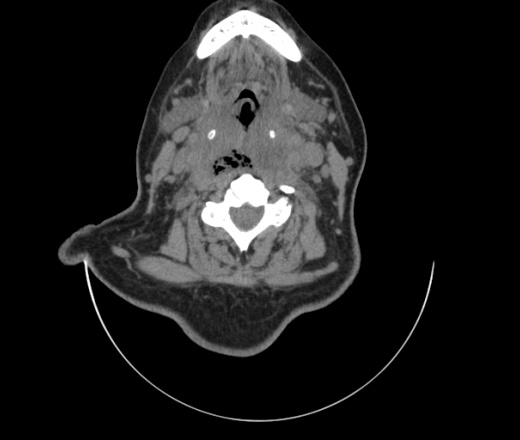

Женщина поступила в х/о спустя 4 дня после того как при употреблении карася подавилась костью.

Наличие газа в средостении на протяжении тел С2-С6 (медиастинальна эмфизема); рыбная кость на уровне тела С6.

При всем уважении, но говорить о медиастинальной эмфиземе, оценивая мягкие ткани шеи, как-то слишком резко. На мой взгляд, это ретрофарингеальное пространство.

Эвакуировали почти 100мл гноя. Но кость не смогли найти. Думаю что она даст дальнейшее ослоднение. Эндоскопически за черпалонадгортаной звязкой не смогли зайти в пищевод, все мягкие ткани отечные, просвет пищевода сдавлен. По всей видимости параэзофагеальная клетчака тоже задействована. Эмпиема, если ее можно так назвать, незнаю как правильно дошла до уровня яремной вырезки. Чем закончиться напишу. Ждем медиастинита.

Флегмона заглоточного пространства шеи, только операция, флегмоны вскрывают. Риск медиастинита.

Согласен с Вами; конечно, наличие газа в клетчатке ретрофарингеального пространства (затмение с опечаткой..). К сожалению, процесс "продвигается" к медиастиниту. Но почему никто, не отмечает наличие рыб. кости; или это для Всех очевидно?

Так вы уже отметили. Хотя ориентировал бы не скелетотопически, а на перстнечерпаловидный сустав.

Кость то мы сразу выявили, размеры где то 17*2мм, но ее так и не получается найти в этой каше